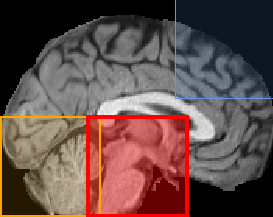

Patch-based Predictions When we use a single patch as input, the results are highly dependent on the area of the brain where the patch is extracted from. We train 27 ResNets for 27 patches, achieving a MAE from around 2.5 to 4.2 years. The patches with the best performance are the ones that include the ventricles or the hippocampus, with MAEs of less than 2.5 and 2.7 years, respectively, and score of 0.80 and 0.76, respectively, as well as patches that include parts of these regions. On the contrary, patches that contain substantial amounts of background perform much worse with a MAE of 3.5-4.2 years and an score of 0.15-0.6. In Figure 3, various patches, colored based on the performance of the corresponding models, are illustrated as part of a whole brain slice.

Based on the results, we conclude that the patches that include parts of the ventricles and the hippocampus tend to predict the age of the subject more accurately with a MAE of less than 3 years, thus our results are consistent with the existing literature [30]. The MAE in some of these cases is lower than that for the baseline network which utilizes the volume of the whole brain, proving that not all parts of the brain are needed for an accurate prediction. Therefore, less computational effort is required for comparable results. On the other hand, patches that include part of the background do not perform as accurately. We observe that although the brain shrinks while age increases, the networks do not manage to capture the changes in the cerebral cortex as accurately. An explanation for this could be the way the images are registered, which reduces size differences between brains, or the relatively small range of existing ages in the dataset, especially of ages beyond 65 years when atrophy tends to accelerate [8]. Furthermore, the use of patches provides a visualization of the parts of the brain that are valuable for age prediction, leading to a more understandable prediction. Although the patches are big and do not provide detailed localization, this work is the first step towards an interpretable and localized brain age estimation. As our next step, we will use smaller patches (e.g. sized 32x32x32 or 16x16x16), either from the whole brain or from the best-performing patches. More localised detection of a deviation from normal trajectories may also be useful for the automatic detection of more focal pathologies such as ventricular enlargement in hydrocephalus or hippocampal atrophy in temporal lobe epilepsies [17].